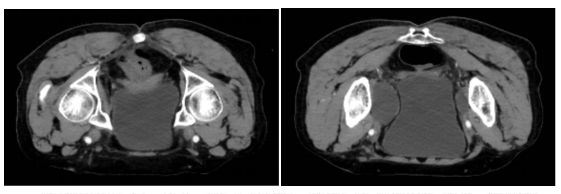

2.病史:患者于2024年7月15日因“阴道不规则流血”就诊于兰州市妇幼保健院,行宫腔镜检查+诊刮术,诊刮病检示:(宫腔)子宫内膜样腺癌,(宫颈)子宫内膜样腺癌。于2024-07-30在全麻下腹腔镜下行“全子宫切除+双侧附件切除+双侧卵巢动静脉高位结扎+盆腔淋巴结清扫术”。术后病理(65807)(全切子宫+双侧附件+左右侧盆腔淋巴结):1.子宫内膜癌,(结合免疫组化倾向子宫内膜浆液性癌),癌组织大小1.7x1xO.8cm,癌组织侵及浅肌层<1/2,左、右宫旁未见癌组织。脉管内未见癌栓。2.子宫平滑肌瘤,3.慢性宫颈炎,4.双侧卵巢未见明显异常,5.左侧盆腔检出淋巴结组织16枚,转移率0/16,右侧盆腔检出淋巴结组织12枚,转移率0/12。病理分期:FIGO Ia期。免疫组化:65807-9 ER(弱+ 1%),PR(弱+ 1%),Her-2(2+),P16(弥漫+),PAX-8(+),PAx-2(+),WT-1(-),CA-125(+),P53(野生型),Ki-67 index 40%, MLHI(+)MSH2(+),MSH6(+),PMS2(+),提示不支持Lynch综合症相关子宫内膜癌。术中(盆腔冲洗液)未查见恶性细胞。于2024-8-7在甘肃省人民医院行病理切片会诊(240514)(子宫、双侧附件及盆腔淋巴结切除术标本切片):1、子宫内膜癌,浆液性癌;侵及浅肌层(<内1/2层)。双宫旁未见癌;未见脉管癌栓。2、慢性宫颈及宫颈内膜炎。3、双卵巢、输卵管组织结构未见特殊,未见癌。4、淋巴结未见转移癌(左盆腔0/16;右盆腔0/12)。分子分型:P53突变型(建议DNA测序验证),病理学分期:FIGO IIC期(FIGO 2023子宫内膜癌分期)。备注:免疫组化染色结果显示:错配修复蛋白功能完整(pMMR),P53提示突变型可能。后分别于2024-08-08、2024-09-06兰州市妇幼保健院给予紫杉醇210mg d1 ivgtt ,卡铂500mg d1 ivgtt 2周期化疗,过程顺利,无特殊不适,

子宫内膜癌术后光子放疗 总剂量46Gy/23f

子宫内膜癌腔内后装治疗 总剂量12Gy/2f

同步白蛋白结合型紫杉醇+卡铂化疗